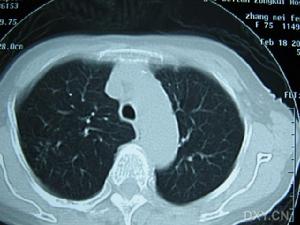

此型是繼發性肺癆的主要類型,肺部有滲出、浸潤和不同程度的乾酪壞死及空洞形成。多見於青年,好發於肺的尖部和下葉背段。X線可表現片狀、雲絮狀陰影,密度不均,可有空洞及纖維索條狀陰影。乾酪性肺炎是浸潤型肺癆的重型,X線表現以肺葉或肺段分布的大片狀密度增高陰影,臨床表現病情兇險,持續高熱,衰竭,休克。

(4)胸部X線檢查用透視、後前位胸片、前弓位攝片、點片、肺尖部攝片、斷層攝片。

(5)CT選擇性運用CT對肺結核診斷可彌補胸部X線檢查的不足。